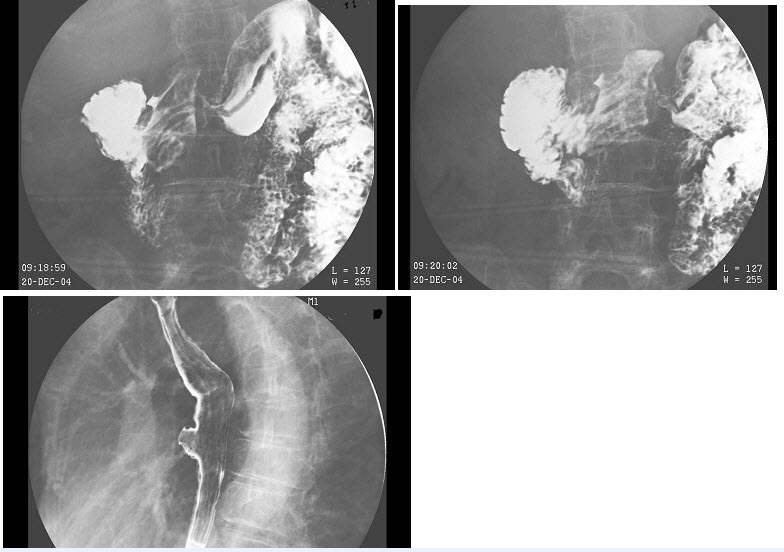

- 多项选择题女,80岁,胃胀痛20多天,体检:剑突下有压痛,结合图像,最可能的诊断为()

- A,E